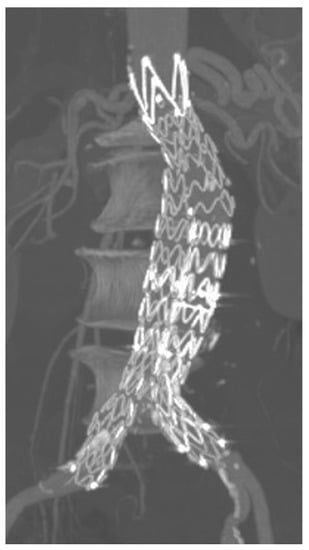

After EVAR, the standard follow-up protocol included physical examination, duplex-ultrasound scan (DUS), and CT at 30 days (Figure 2). DUS was then performed at 3 and 6 months, at 1 year, and yearly thereafter. All patients underwent CT imaging 1 year after the initial procedure, without further CT examinations in the absence of complications detected by yearly DUS follow-up.

Figure 2.

Multiplanar CTA reconstruction confirming good technical success and complete aneurysm exclusion during follow-up.